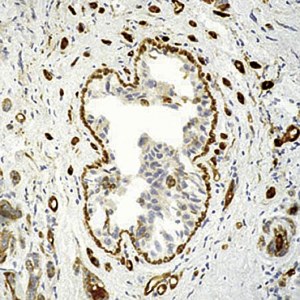

Validation d'anticorps en IHC sur coupes de tissus

Cette analyse est réalisée dans des sections uniques de tissus normaux et cancéreux congelés. => Demande de devis